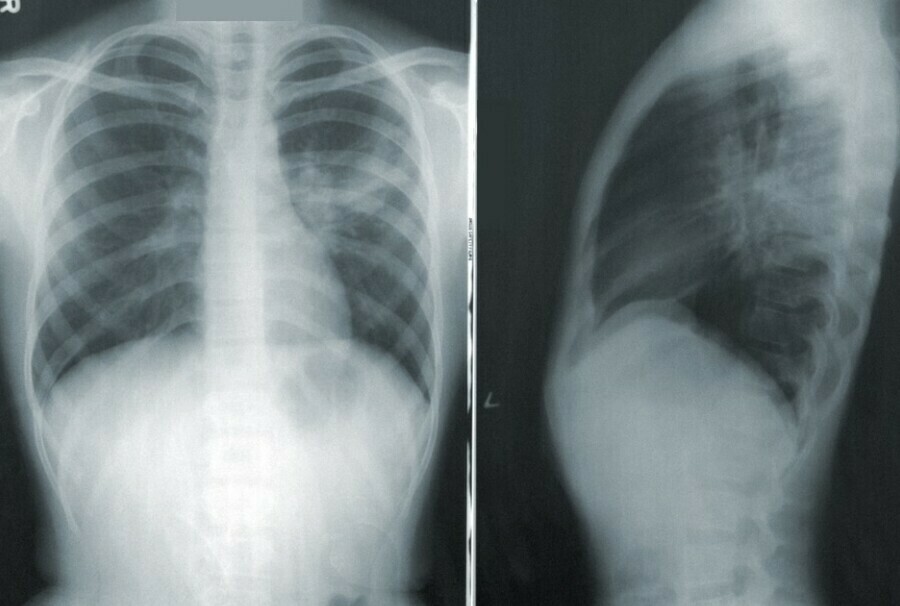

– Стандартом диагностики в данном случае является рентген органов грудной клетки. Методом с более высоким разрешением является компьютерная томография. В определенных ситуациях, если на рентгеновском снимке не совсем понятна картина и есть какие-то сомнения, то КТ может и должна применяться. Но лучевая нагрузка при этом намного выше, чем на обычном рентгене, поэтому решение о выборе метода диагностики должен принимать лечащий врач. Самостоятельно, без назначения, делать рентген или КТ однозначно не стоит.